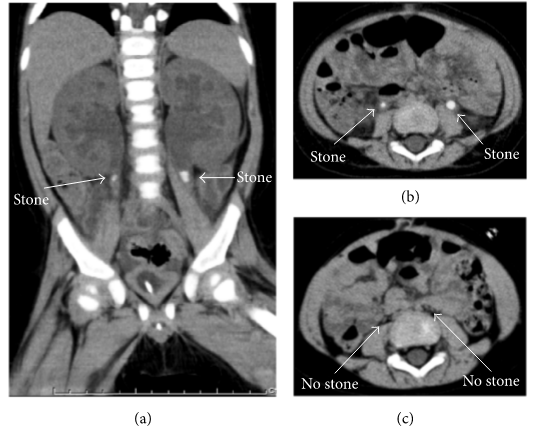

尿道结石与急性病毒性肠胃炎引起婴儿肾功能衰竭3例报道